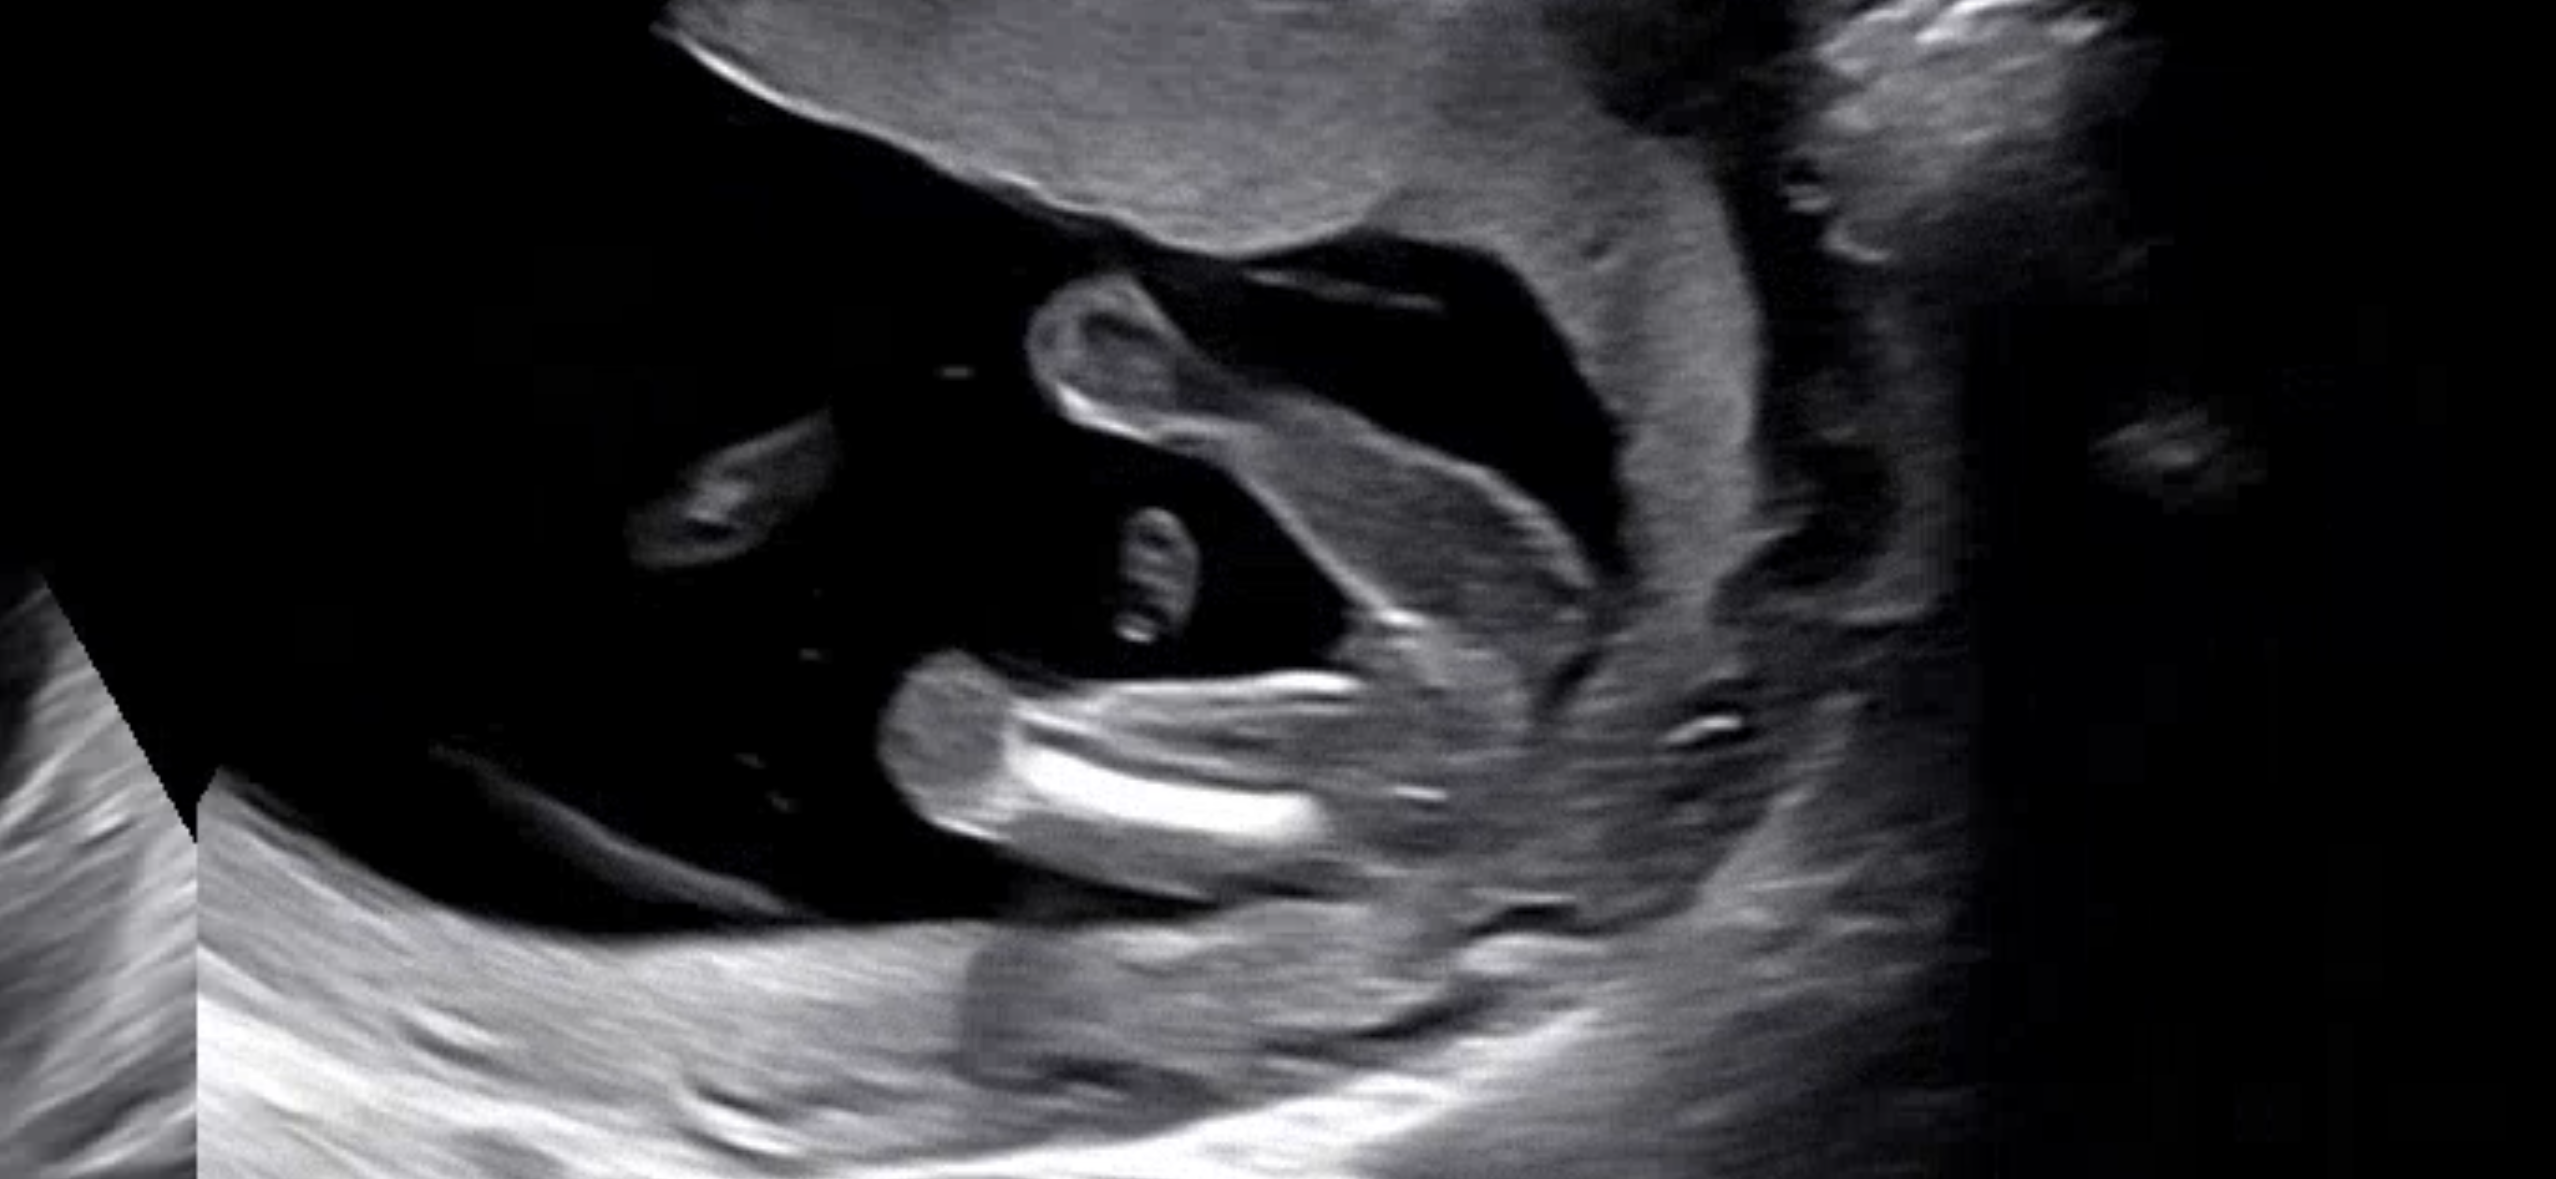

이 정도면 딸이겠죠? 16주 2일이에요!

선생님이 핑크라고 해주시더라구요!